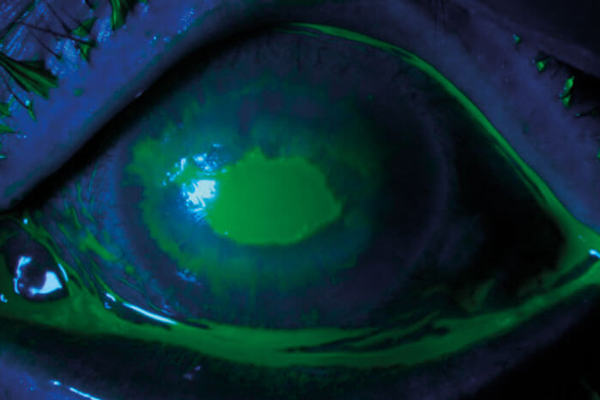

Anaesthetic drops abuse